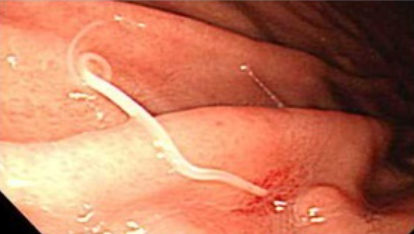

胃に寄生するアニサキス(『厚生労働省オフィシャルホームページ』より)